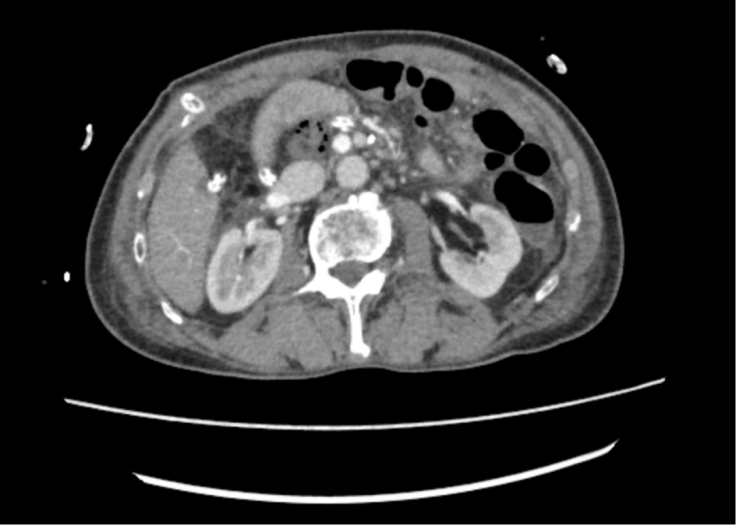

面对复杂的手术区域,郑志鹏主任带领团队迎难而上,依托丰富的腹腔镜外科技术,历时7小时完成手术。术中通过5个小孔,精细解剖肝动脉、门静脉、肠系膜上静脉等多条重要血管,完整切除肿瘤及受侵犯的门静脉,仔细将门静脉缝合,严密对合后的血管通畅无渗血。患者术后第5天恢复饮食,10天后顺利出院,住院时间比传统开腹手术缩短近一半时间,更关键的是,腹部仅留5个0.5-25px小孔,肚子上没有“蜈蚣疤”。

术后CT显示术区干洁